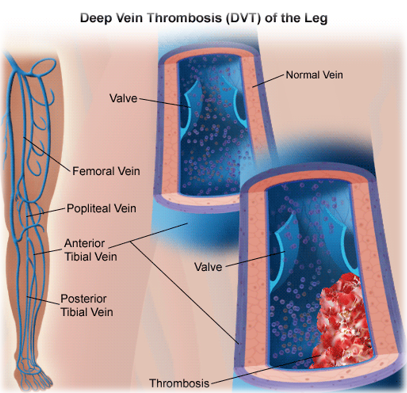

نارسایی دریچه ای در وریدهای عمقی و یا وریدهای پرفوریتور (ناهنجاری های مادرزادی، تغییرات سنی)

ترومبوز وریدهای عمقی و انسداد جریان خون اختلال پمپ عضلانی بدلیل کاهش حرکت عضو یا مفصل مچ پا در اثر فلج